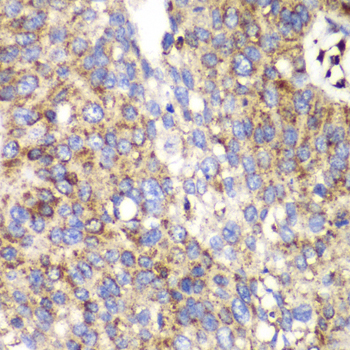

Immunohistochemistry of paraffin-embedded human lung cancer using SPARC antibody at dilution of 1:100 (400x lens).

Immunohistochemistry of paraffin-embedded human liver cancer using SPARC antibody at dilution of 1:100 (400x lens).

Immunohistochemistry of paraffin-embedded human esophageal cancer using SPARC antibody at dilution of 1:100 (400x lens).